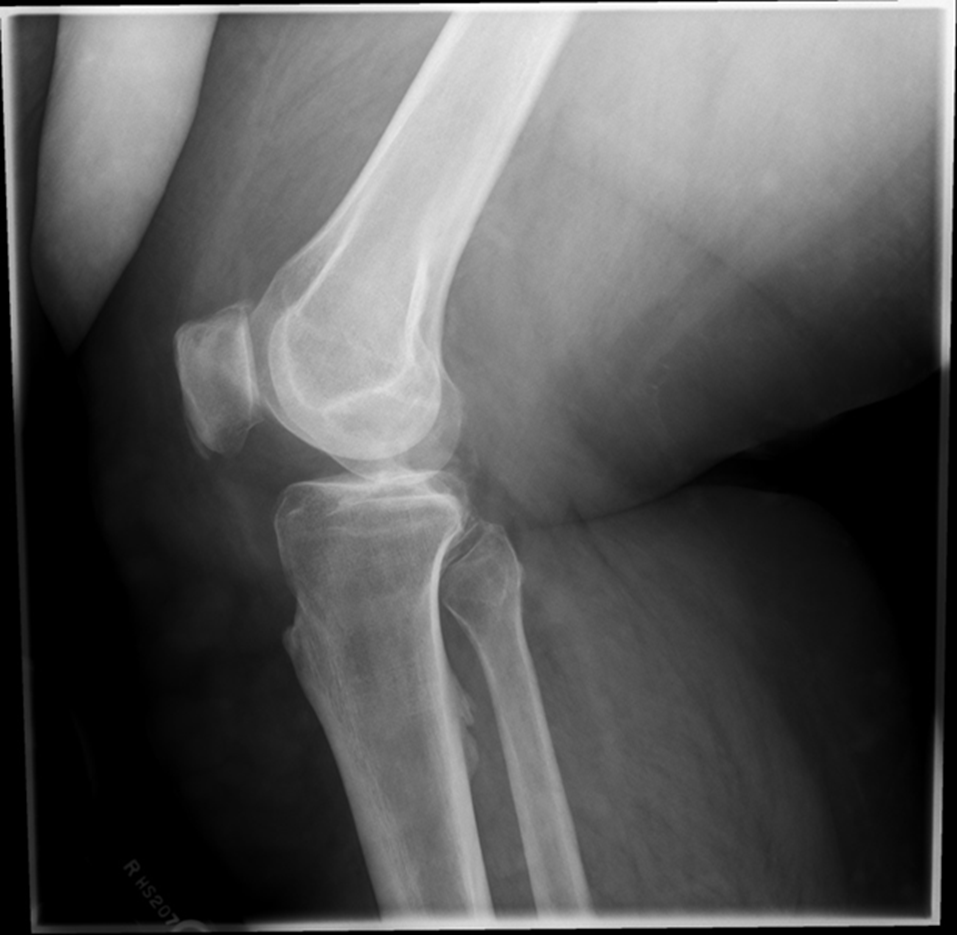

Lateral Rotation, the fibular head is under the tibia, if patella is towards lateral side usually means it is laterally rotated.

Joint space is not open enough

The width of the joint space is not equal

REPEAT FOR LATERAL ROTATION

Not enough superimposition of the fibular head

Patella is in the center! good! equal distance of joint space/platoes which is good

ACCEPTABLE BECAUSE EVERYTHING ELSE IS GOOD! PATIENT COULD HAVE A MORE SEPARATED FIBULAR HEAD! THEIR ANATOMY IS DIFFERENT. CENTERING IS GOOD